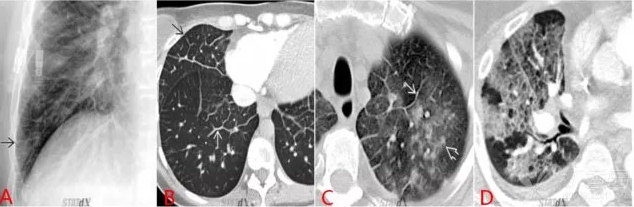

4. 蝶形影/蝙蝠翼样表现

肺水肿在 CT 上的典型表现为弥漫性、边界不清的磨玻璃样表现。

(1)心源性肺水肿发生时,在同一水平面上越接近左心房,肺血管内静水压越高,故而肺水肿在心脏周围更明显,即中心 > 外周,形成 X 片上大家所熟悉的蝶形影样表现,而在 CT 上这一征象也被有的教科书称之为蝙蝠翼样改变。

(2)非心源性肺水肿的发生:主要由于肺泡膜-毛细血管壁的直接损伤所致,故而越接近外周,损伤越多越严重,肺泡渗出也越明显,故非心源性肺水肿外周 > 中心。

QQ浏览器截图20200505212739.png

图 6 心源性肺水肿典型表现:蝶形影/蝙蝠翼样表现

图 6A 显示的是肺水肿患者的普通胸片,可见双肺纹理明显增多,以肺门为中心的弥漫性渗出影。近胸膜处不明显,即蝶形渗出,中心大于外周。

图 6B 为肺水肿患者的 CT 显像,同样表现为中心大于外周的弥漫渗出,称之为蝙蝠翼征。

图 6C 可见双肺弥漫广泛渗出,但近胸膜处渗出影明显多于肺门周围,即外周大于中心,该片为过量使用可卡因导致急性肺水肿。